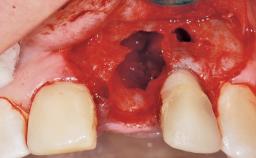

Immediate Flapless Placement of an Implant in a Maxillary Right Lateral Incisor Site

This 43-year-old male patient, a non-smoker, came to our practice because of a fracture of tooth 12 caused by a bicycle accident. Due to the combined para- and infrabony crown and root fracture, tooth extraction, and subsequent implant placement were suggested to the patient as the therapy of choice. The patient had high esthetic expectations with regard to the treatment outcome and asked for an immediate fixed provisional restoration. His individual esthetic risk profile summed up to a medium esthetic risk.

Soft Tissue Anatomy Intact Defective

Socket Integrity Sufficient, with intact bone walls

Bone Volume Sufficient, with intact walls